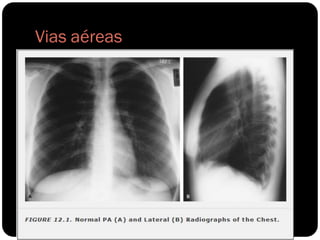

Vias aéreas

TRAQUÉIA

Brônquios

Bronquíolos

Alvéolos

 Anéis cartilaginosos em forma de C;

 Membrana traqueal posterior: músculo e tecido

conjuntivo;

 Identações na parede lateral esquerda da

traquéia distal  arco aórtico;

 12cm;

 Transparência cilíndrica da cartilagem cricóide

até os brônquios principais;

 Normal ligeiro desvio da traquéia para a direita;

 Linha paratraqueal direita (interface do LSD

com parede lateral direita da traquéia): não

deve ultrapassar 4mm ;

 Parede paratraqueal esquerda circundada por

tecido adiposo e vasos mediastinais 

normalmente não é vista na radiografia;